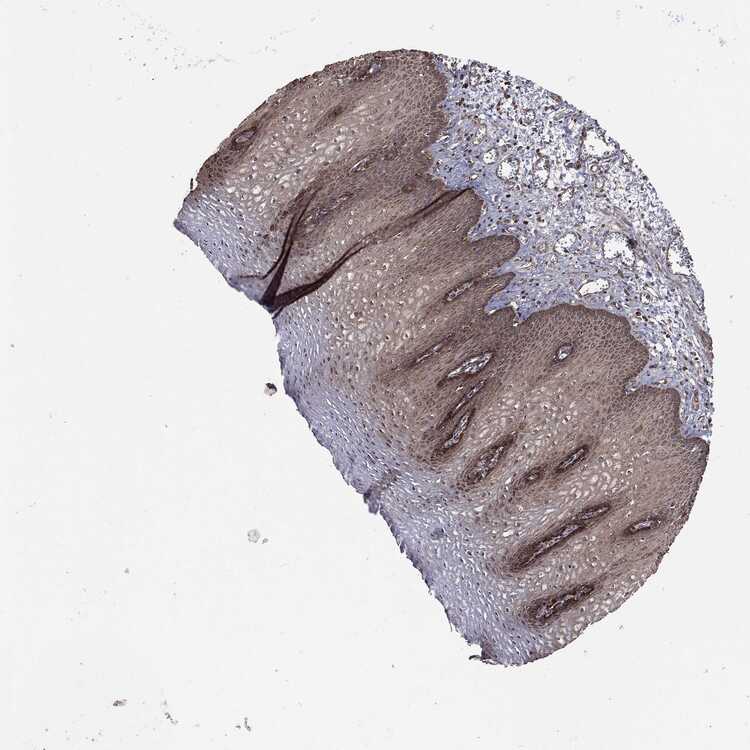

TISSUE PRIMARY DATA ESOPHAGUS Show tissue menu

Esophagus

ESOPHAGUS - Expression summary

ESOPHAGUS - Antibody stainingi

Antibody staining in the annotated cell types in the current human tissue is reported as not detected, low, medium, or high, based on conventional immunohistochemistry profiling in selected tissues. This score is based on the combination of the staining intensity and fraction of stained cells.

Each image is clickable and will lead to virtual microscopy that enables deeper exploration of all samples and also displays staining intensity scores, fraction scores and subcellular localization as well as patient and tissue information for each sample.

Antibody CAB069425Antibody CAB080053Antibody CAB080065Antibody CAB080070Antibody CAB080081Antibody CAB080095Antibody CAB080097

Squamous epithelial cells MediumHighLowMediumNot detectedMediumHigh